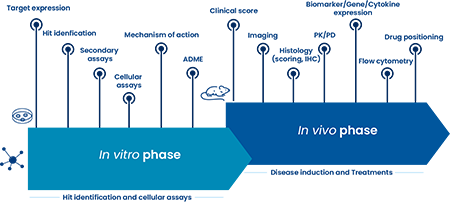

A typical screening cascade in an integrated inflammation program

We show the data of one of the selected preclinical candidate (ODS-002), which was prepared and tested via multiple step. This case study is a concrete example of our integrated service offering INPACT PoC Inflammation.

INPACT PoC Inflammation is an integrated preclinical pharmacology package to speed your selected drug candidate to the clinic. It combines the following capabilities to support your therapeutic discovery and innovation programs: